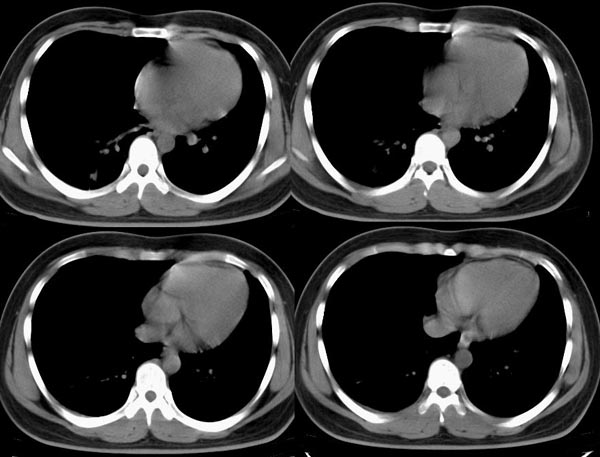

m21y既往体健,否认结核、支扩等病史;1周前患上感,无明显咳嗽,自觉无明显不适。单位体检透视时发现右侧液气胸!cr及ct如下(肺组织窗:l:-598hu w:1132hu):请大家会诊!!

右侧巨大含气囊性病变,壁薄、光整、其外侧见气体。右肺压迫性肺不张、胸腔内见少量积液。纵隔向左侧移位。左肺未见异常。诊断:1.右侧含气肺囊肿(先天性)。2.右侧液气胸。(少量液体)3.右肺压迫性肺不张。我也遇见一例这样的病人。女性。股骨外伤就诊。常规胸片发现右侧囊性病变。

本例病史无胸闷、气短等症状;影像学示气囊壁厚,病变区透亮度介于气胸与肺大皰之间,内无发丝样阴影,不伴有周围肺气肿;囊肿位于肺表面。壁厚,张力不高,在游离、切除过程中并不破裂,可与肺大皰相区别。另外,病人有长期吸烟史,每日30余支,术中却见肺表面如同正常小儿肺,无炭末、粉尘沉积,因此,该病可能为自幼存在的先天性疾病。